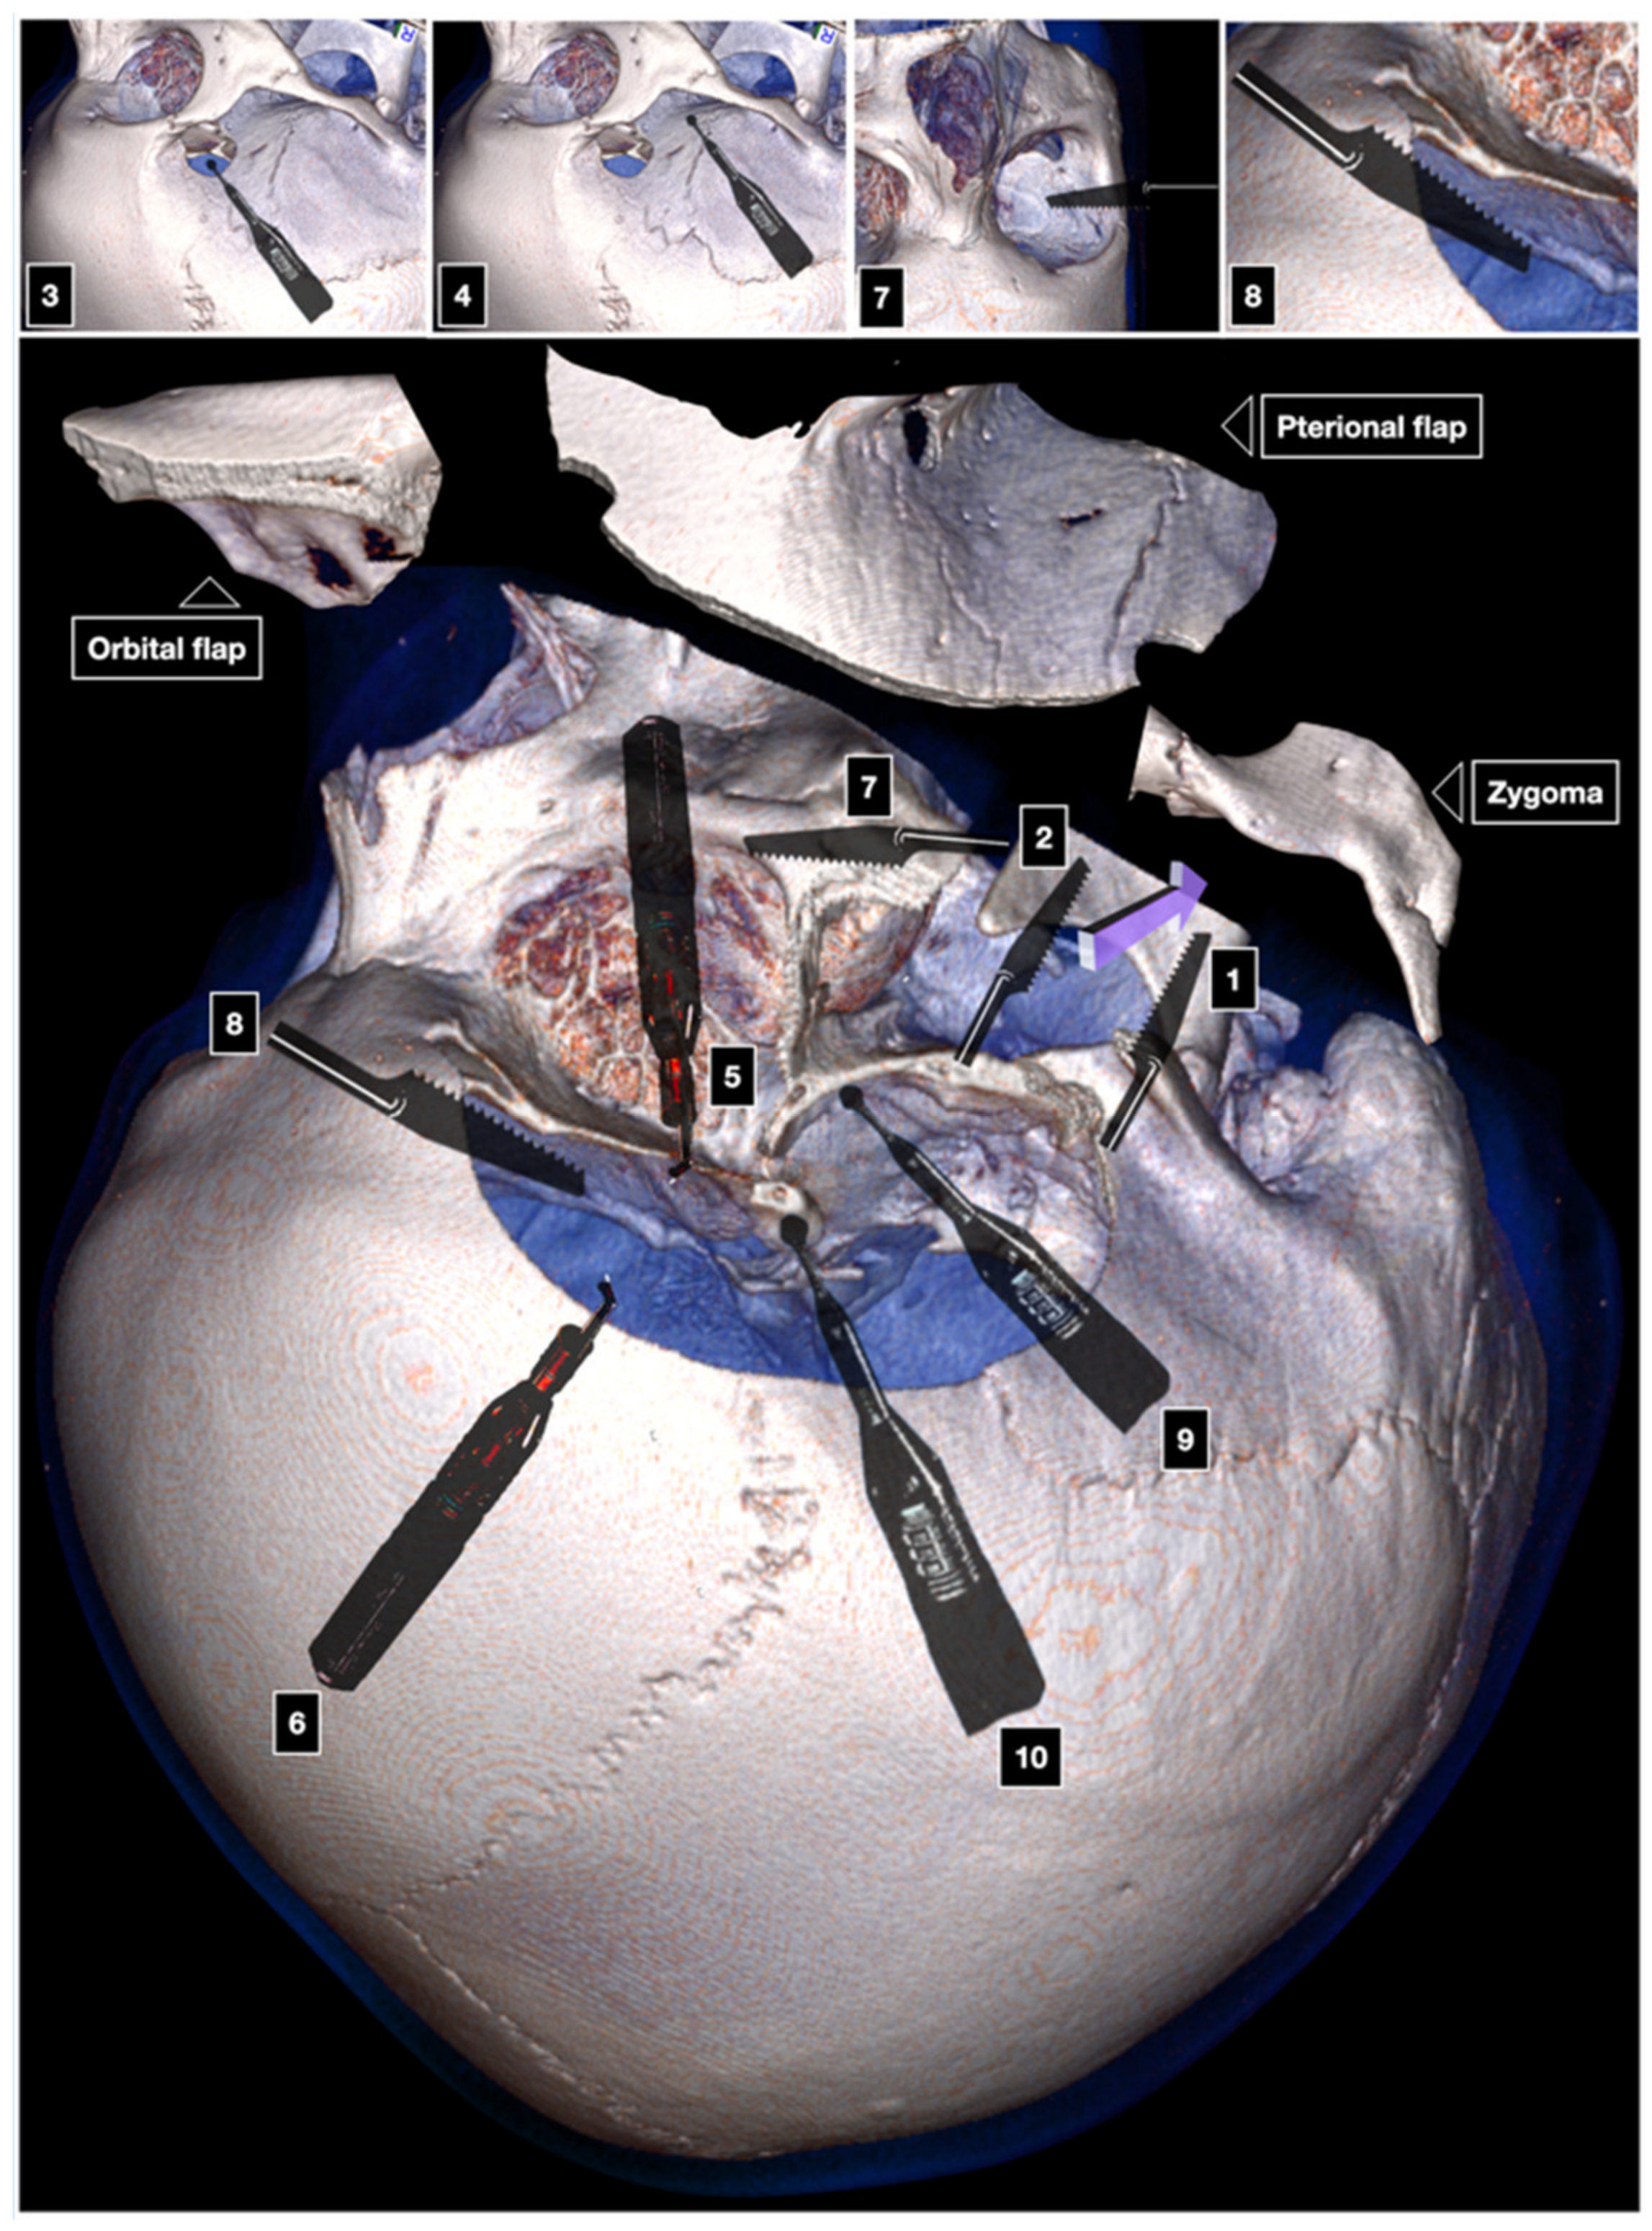

Three-Piece Cranio-Orbito-Zygomatic Craniotomy